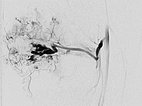

Die digitale Subtraktionsangiographie (DSA) des Knies (links a.-p. Projektion, links seitliche Projektion) zeigt eine AVM mit einem eher kugeligen, aneurysmatischen Nidus sowie einen weiteren Nidus intraossär im lateralen Tibiaplateau. Dieser sehr kugelige, aneurysmatische Nidus zusammen mit der schmerzhaften, progredienten Raumforderung lässt an ein PTEN-Hamartom denken.

DSA-Bild (roadmap-Technik) während der erneuten Embolisation zeigt schwarz im Bild das frisch injizierte neue, zusätzliche Embolisat.